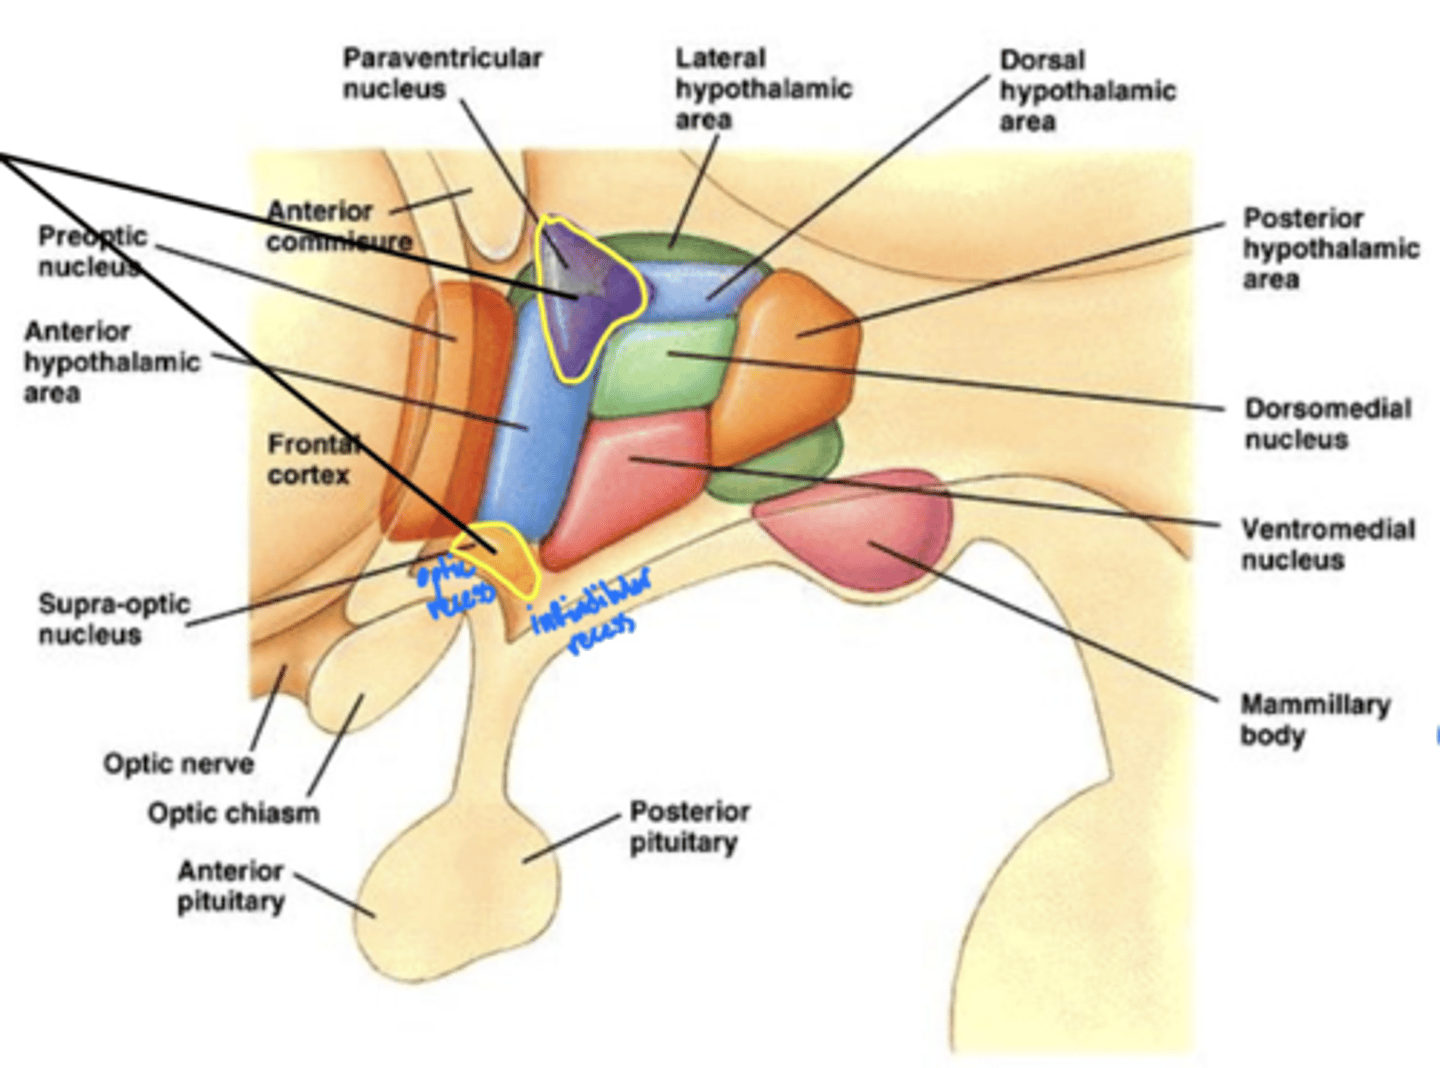

What is the function of the hypothalamus?

homeostasis

What is the hypothalamus just superior to?

1. optic chiasm

2. pituitary gland

What nuclei of the hypothalamus produce hormones for the pituitary gland?

1. paraventricular nucleus

2. supra-optic nucleus

Where is the hypothalamus in relation to the thalamus?

anteroinferior (in front and below)